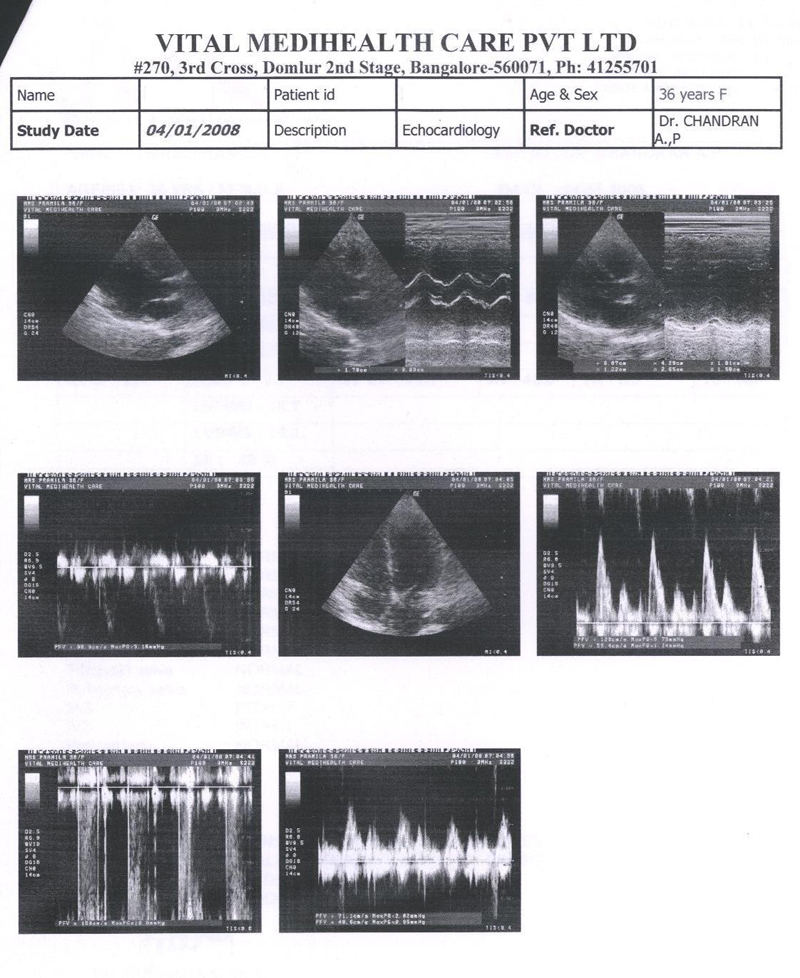

Echocardiography was done indicating a normal heart and patient is un symptomatic. Final Echocardiography was done and shown in FIG 4

FIG 4:- Echocardiography report of 4th JAN 2008